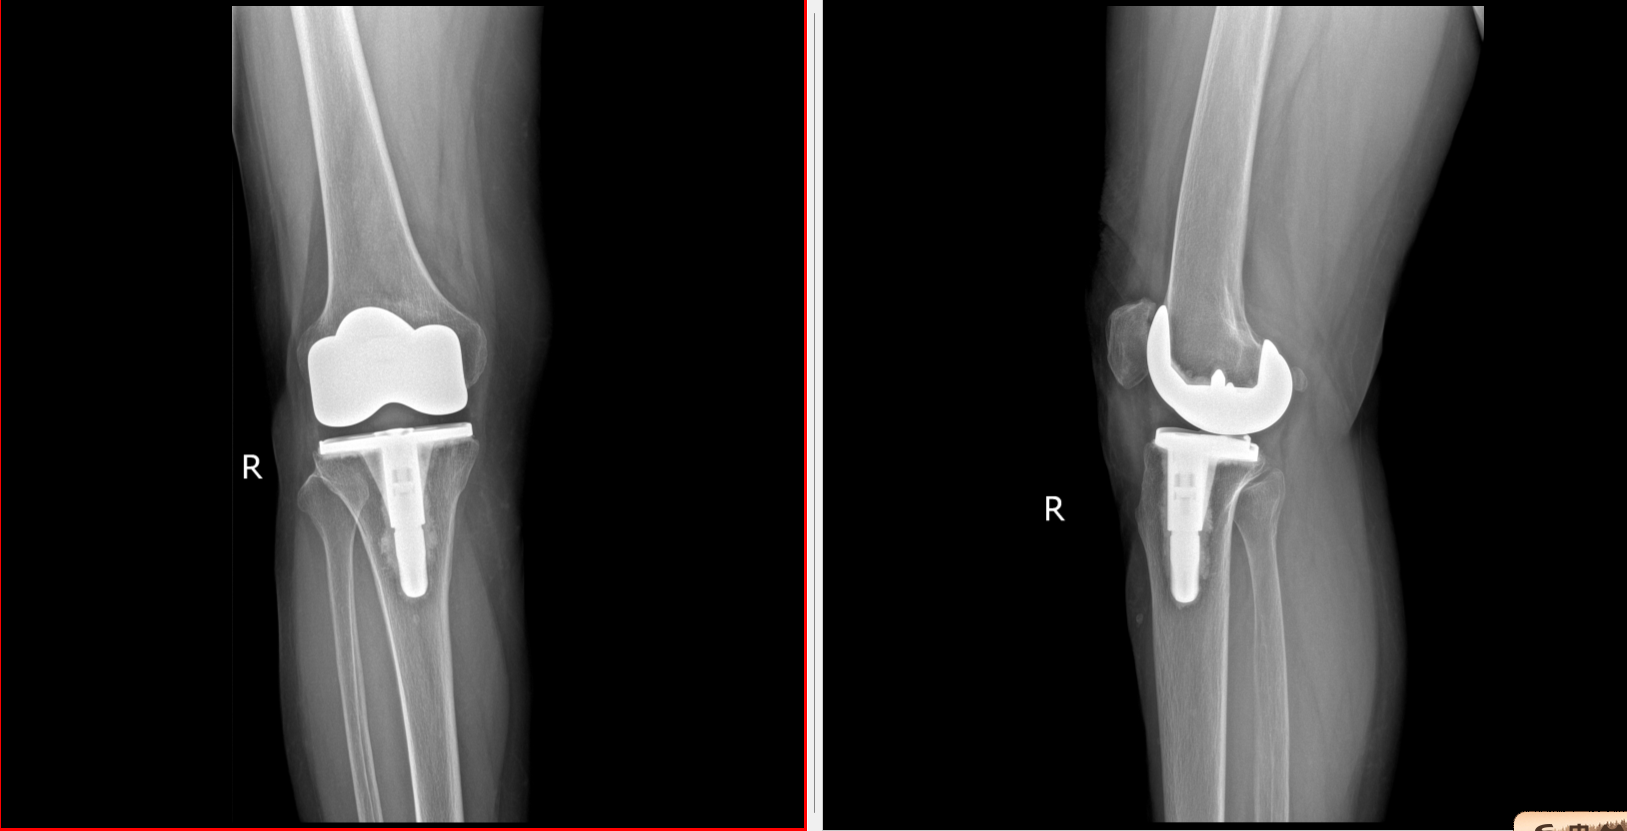

术前DR片

据悉,该患者一年前于外院接受膝关节置换术后,持续出现行走疼痛,并伴有关节卡压、伸直与弯曲困难等功能障碍,严重影响了日常生活。为解决病痛,患者曾辗转多地多家医院求医,并接受过关节镜松解手术,但效果不佳,疼痛症状未能得到有效缓解。